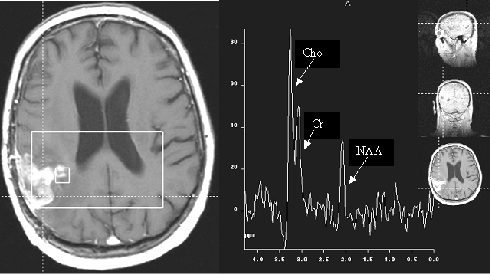

Proton magnetic resonance (MR) spectroscopy is a well-established technique for studying the chemical composition of structures. Hence, it provides a potential noninvasive method of analyzing the metabolite content of normal and diseased brain. A typical MR spectroscopy plots the relative concentration of a given metabolite versus the effect that the metabolite has on the rotational frequency of protons within the sample (measured in parts per million [ppm]). Several standard peaks are measured by MR spectroscopy of the brain in routine clinical J:lractice: N-acetylaspartate (NAA) is a marker for neuronal viability, creatine is generally used as an internal marker or reference, and choline is involved in the synthesis of phospholipids and is a marker of cellular turnover. The presence of additional peaks can be a helpful differential feature in certain disease states: glutamine and glutamate are astrocyte markers and may be altered in the setting of neuronal damage, myoinositol is an astrocyte marker elevated in Alzheimer disease, and lipids and lactate are elevated in inflammatoy processes and in necrotic tissue.